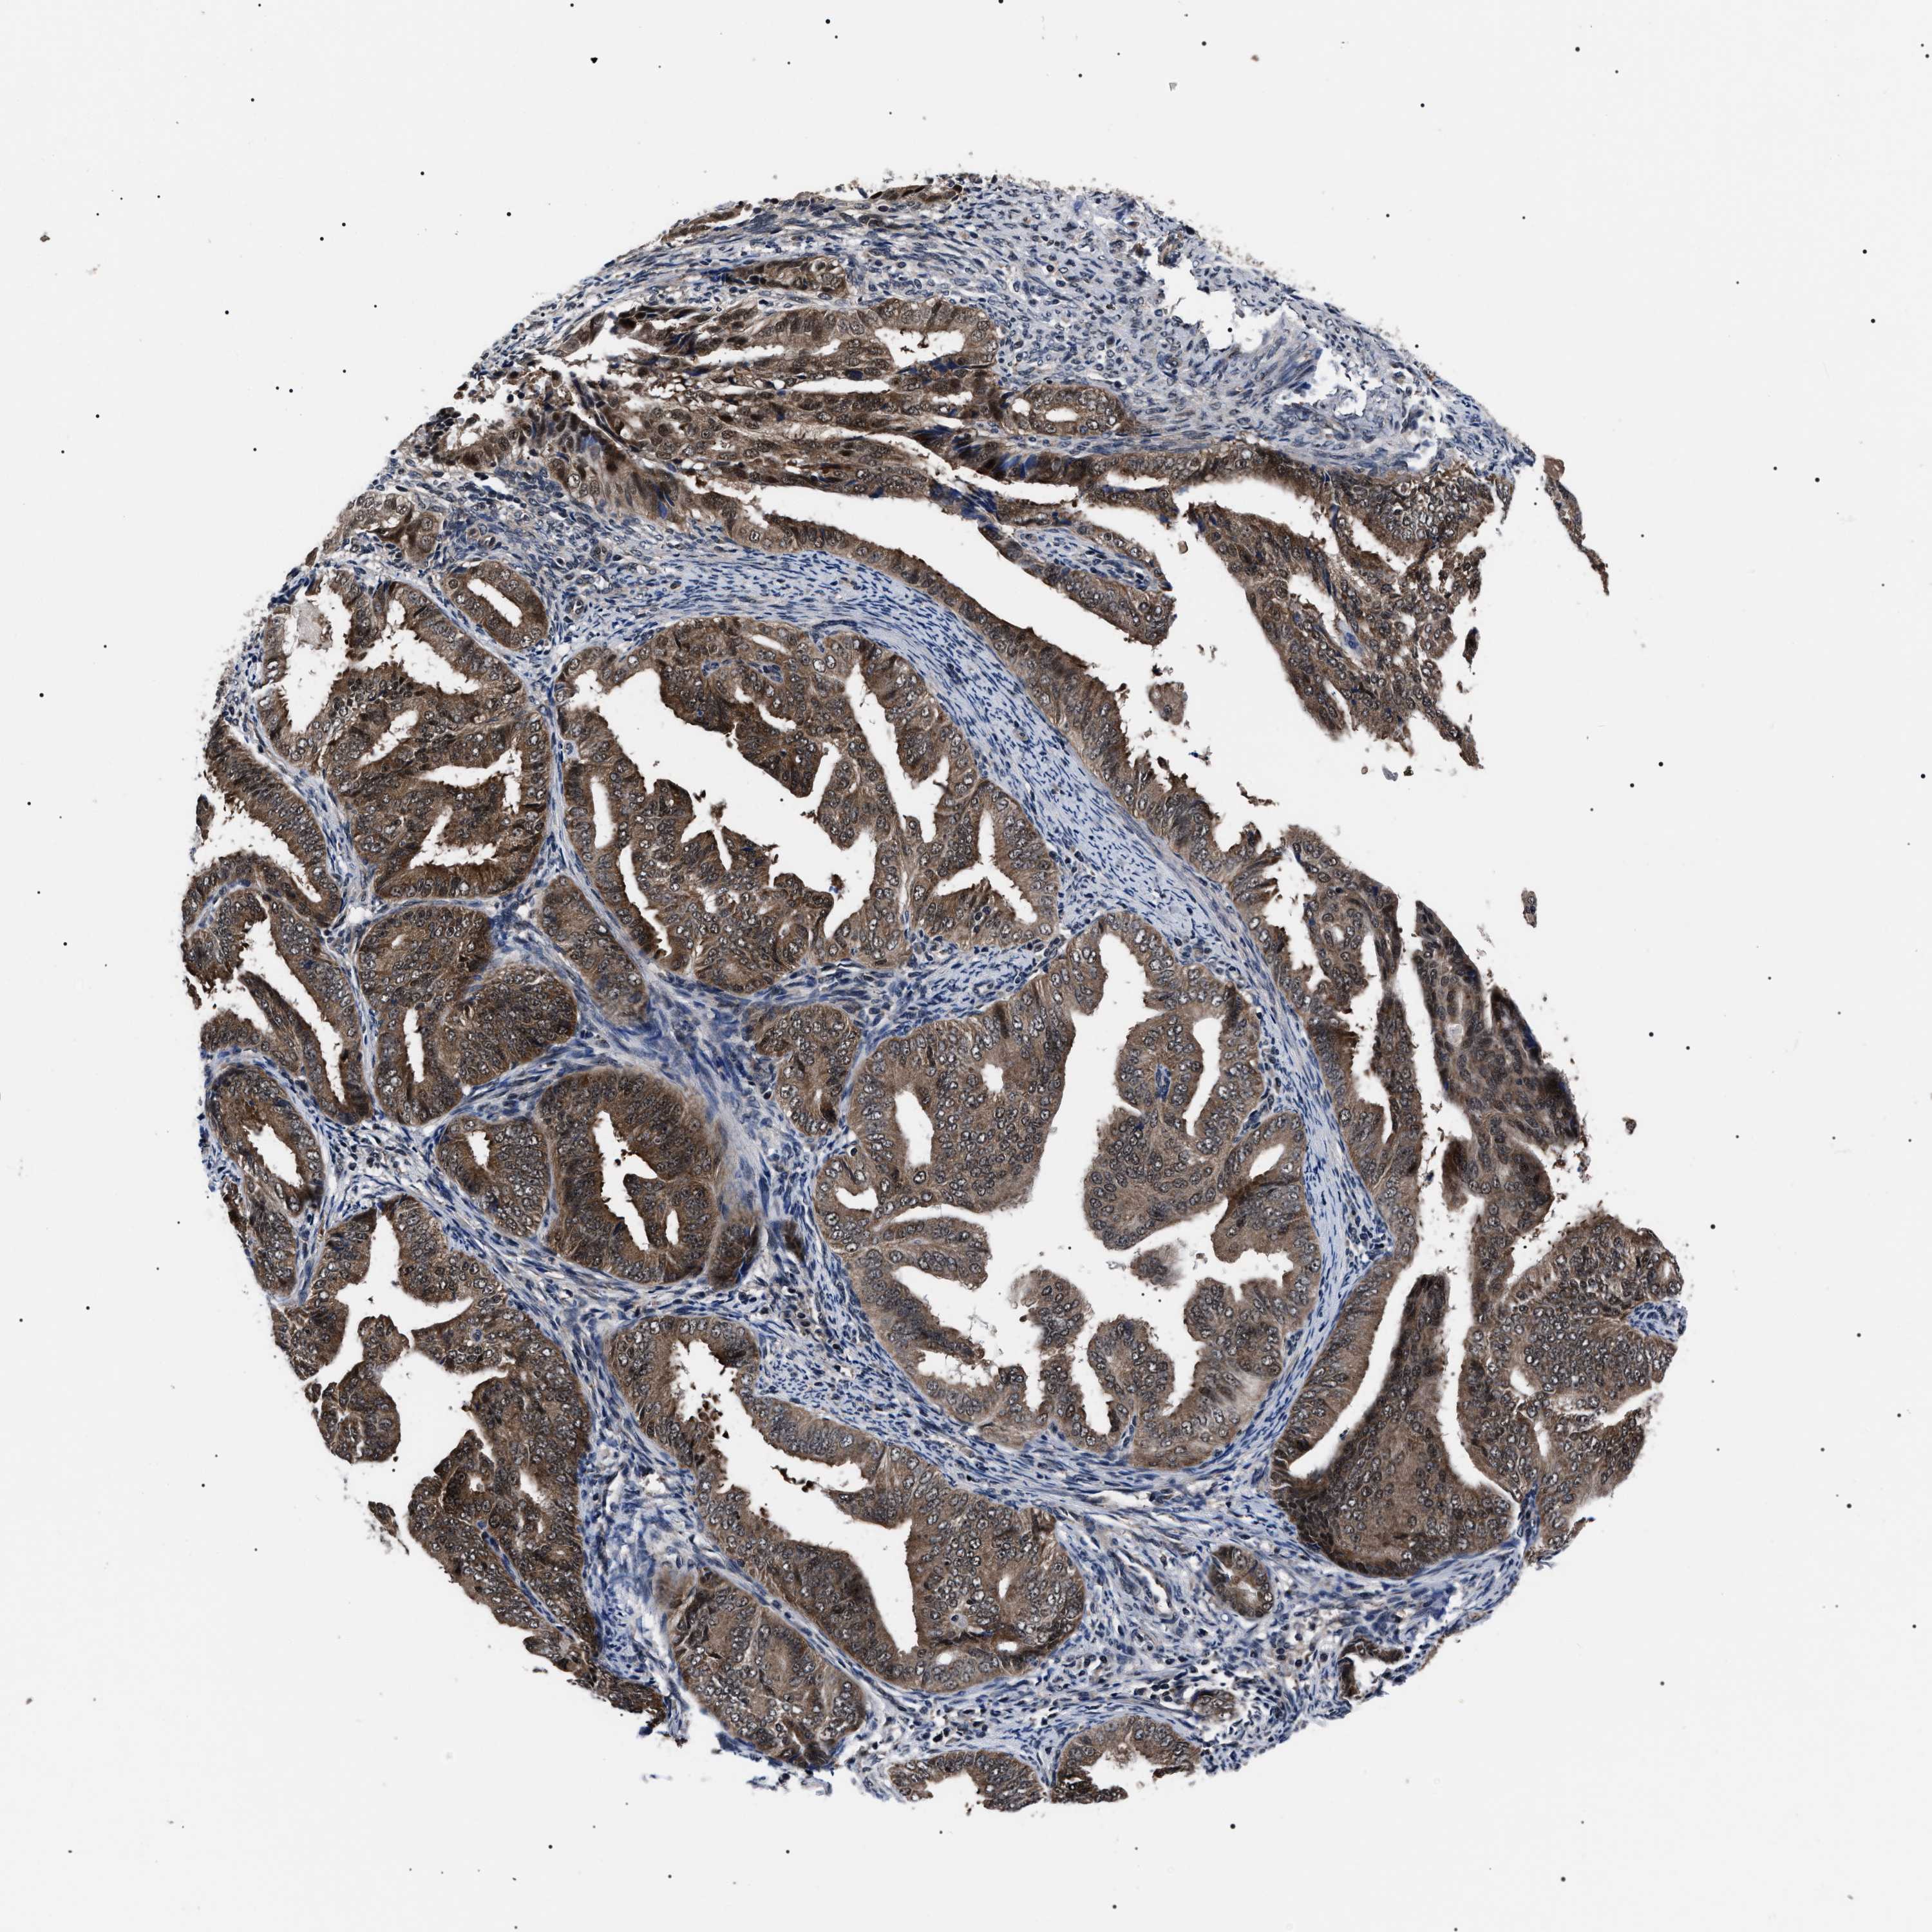

ENDOMETRIAL CANCER - Protein expressioni

A mouse-over function shows sample information and annotation data. Click on an image to view it in a full screen mode. Samples can be filtered based on level of antibody staining by selecting one or several of the following categories: high, medium, low and not detected. The assay and annotation is described here.

Note that samples used for immunohistochemistry by the Human Protein Atlas do not correspond to samples in the TCGA dataset.

Antibody stainingi

Antibody staining in the annotated cell types in the current human tissue is reported as not detected, low, medium, or high, based on conventional immunohistochemistry profiling in selected tissues. This score is based on the combination of the staining intensity and fraction of stained cells.

Each image is clickable and will lead to virtual microscopy that enables deeper exploration of all samples and also displays staining intensity scores, fraction scores and subcellular localization as well as patient and tissue information for each sample.

Antibody HPA061698

Antibody CAB020680

Antibody CAB069395

Staining

High

Medium

Low

Not detected

Intensity

Strong

Moderate

Weak

Negative

Quantity

>75%

75%-25%

<25%

None

Location

Nuclear

Cytoplasmic/membranous

Cytoplasmic/membranous,nuclear

Adenocarcinoma, NOS

Adenocarcinoma, metastatic, NOS